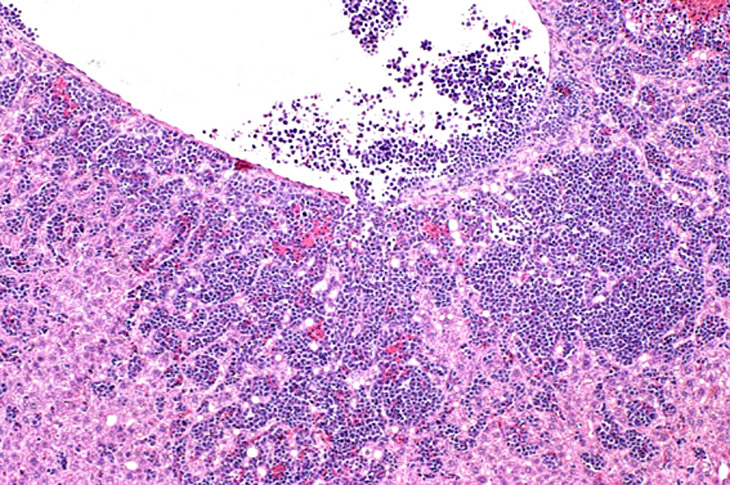

Erythroleukemia is a spontaneous hematopoietic neoplasm of Tg.AC mice characterized by marked hepatomegaly. The affected liver is infiltrated by metarubricytes and less differentiated erythroid precursors.

Low magnification of erythroleukemic infiltrates in the liver.